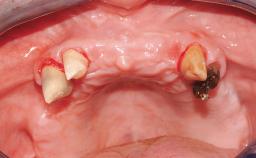

Conventional Loading of Eight Implants in the Maxilla and Final Restoration with a Full-Arch Gold-Ceramic FDP

A 35-year-old Caucasian female presenting with advanced periodontal disease involving both the maxillary and the mandibular dentition was referred for evaluation. The patient, a non-smoker in good general health, requested treatment for recurrent periodontal abscesses, tooth mobility, and discomfort during chewing, as well as restoration of her missing teeth with a fixed prosthesis to improve mastication and esthetics. All residual maxillary teeth exhibited plaque deposits, deep pockets, bleeding on probing, and class III mobility and were evaluated as hopeless. All residual mandibular teeth except tooth 37 could be maintained after periodontal therapy.

Soft Tissue Contour and Volume Significantly deficient